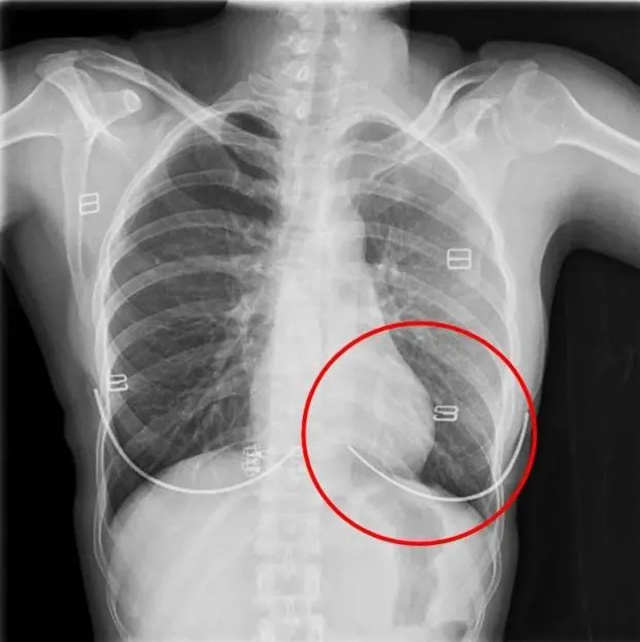

DR是一種比較常規(guī)的基礎影像學檢查方式,適用于人體各部位的健康普查及疾病檢查等優(yōu)勢,在臨床基礎檢查中備受醫(yī)生和患者的青睞。DR體檢車在健康體檢中有著非常重要的地位,由通過電纜串接在一起的探測板、掃描控制器、系統(tǒng)控制及影像顯示器等構成。對比CT檢查而言,DR檢查的價格更低,輻射劑量更小它可以讓疾病預防,微細病變可更好顯示診斷治療提供科學的結果依據(jù)。很多外傷患者都要做DR檢查,來判斷是否骨折或其他的情況。體檢過程中面對DR體檢車做檢查時候需要準備注意什么呢?很多時候大家都有這樣的疑問,身上攜帶的物品是否會對圖像造成遮擋或給機器帶來干擾?檢查前如何準備才不會影響檢查準確性?